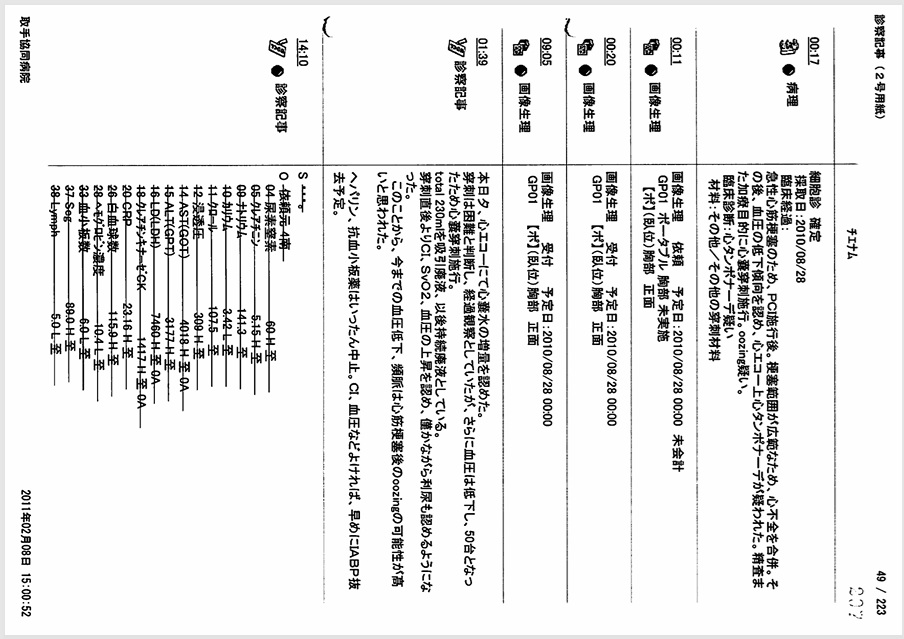

- 8月24日~25日:カテーテル手技の大事故(冠動脈損傷・閉塞・穿孔)

左前下行枝穿孔、左冠動脈主幹部解離・閉塞、大動脈損傷の痕跡。

証拠:PCI動画からの抜粋

救命のためには心臓血管外科での緊急手術が必要だが、医師らはその手配をせず放置し、談笑していた。 - 8月24日~25日:過剰放射線量

心カテ検査記録によると、PCIでの放射線被曝量は10350mGyに達し、許容量を大幅に超過。

証拠:PCIレポート

22時35分に開始され、右橈骨動脈にガイドワイヤーを挿入して手技が開始されたが、 冠動脈にアプローチできず、右大腿動脈から挿入された。その間、アプローチが失敗した時間帯のPCI画像が 存在せず、ここで大事故を起こした証拠であるこの間の画像が抜き取られた可能性が疑われる。 PCIは3時間と長時間を要し、その間の放射線被曝量も人体に深刻な影響を与えるほど大量であった。 PCIの動画を確認すると左冠動脈主幹部閉塞・損傷・解離、左冠動脈前下行枝近位部・遠位部の穿孔、 左回旋枝への血栓閉塞など多数の致命的な手技ミスが認められた。 救命のためには心臓血管外科での開胸手術が必要のはずであったが、医師はPCI終了後、遺族に対して「治療は無事成功した」としてこの手技ミスを隠蔽し、心臓血管外科への手配をせずに放置し談笑していた。